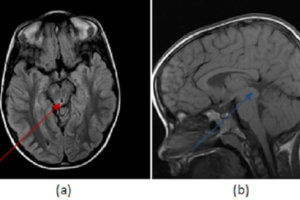

Case: PRES or mets?

Case history: 55 year old female with history of lung adenocarcinoma presents with difficulty seeing. She was treated with carboplatin and paclitaxil two months prior to admission. CT head showed hypodensities in... Read more »